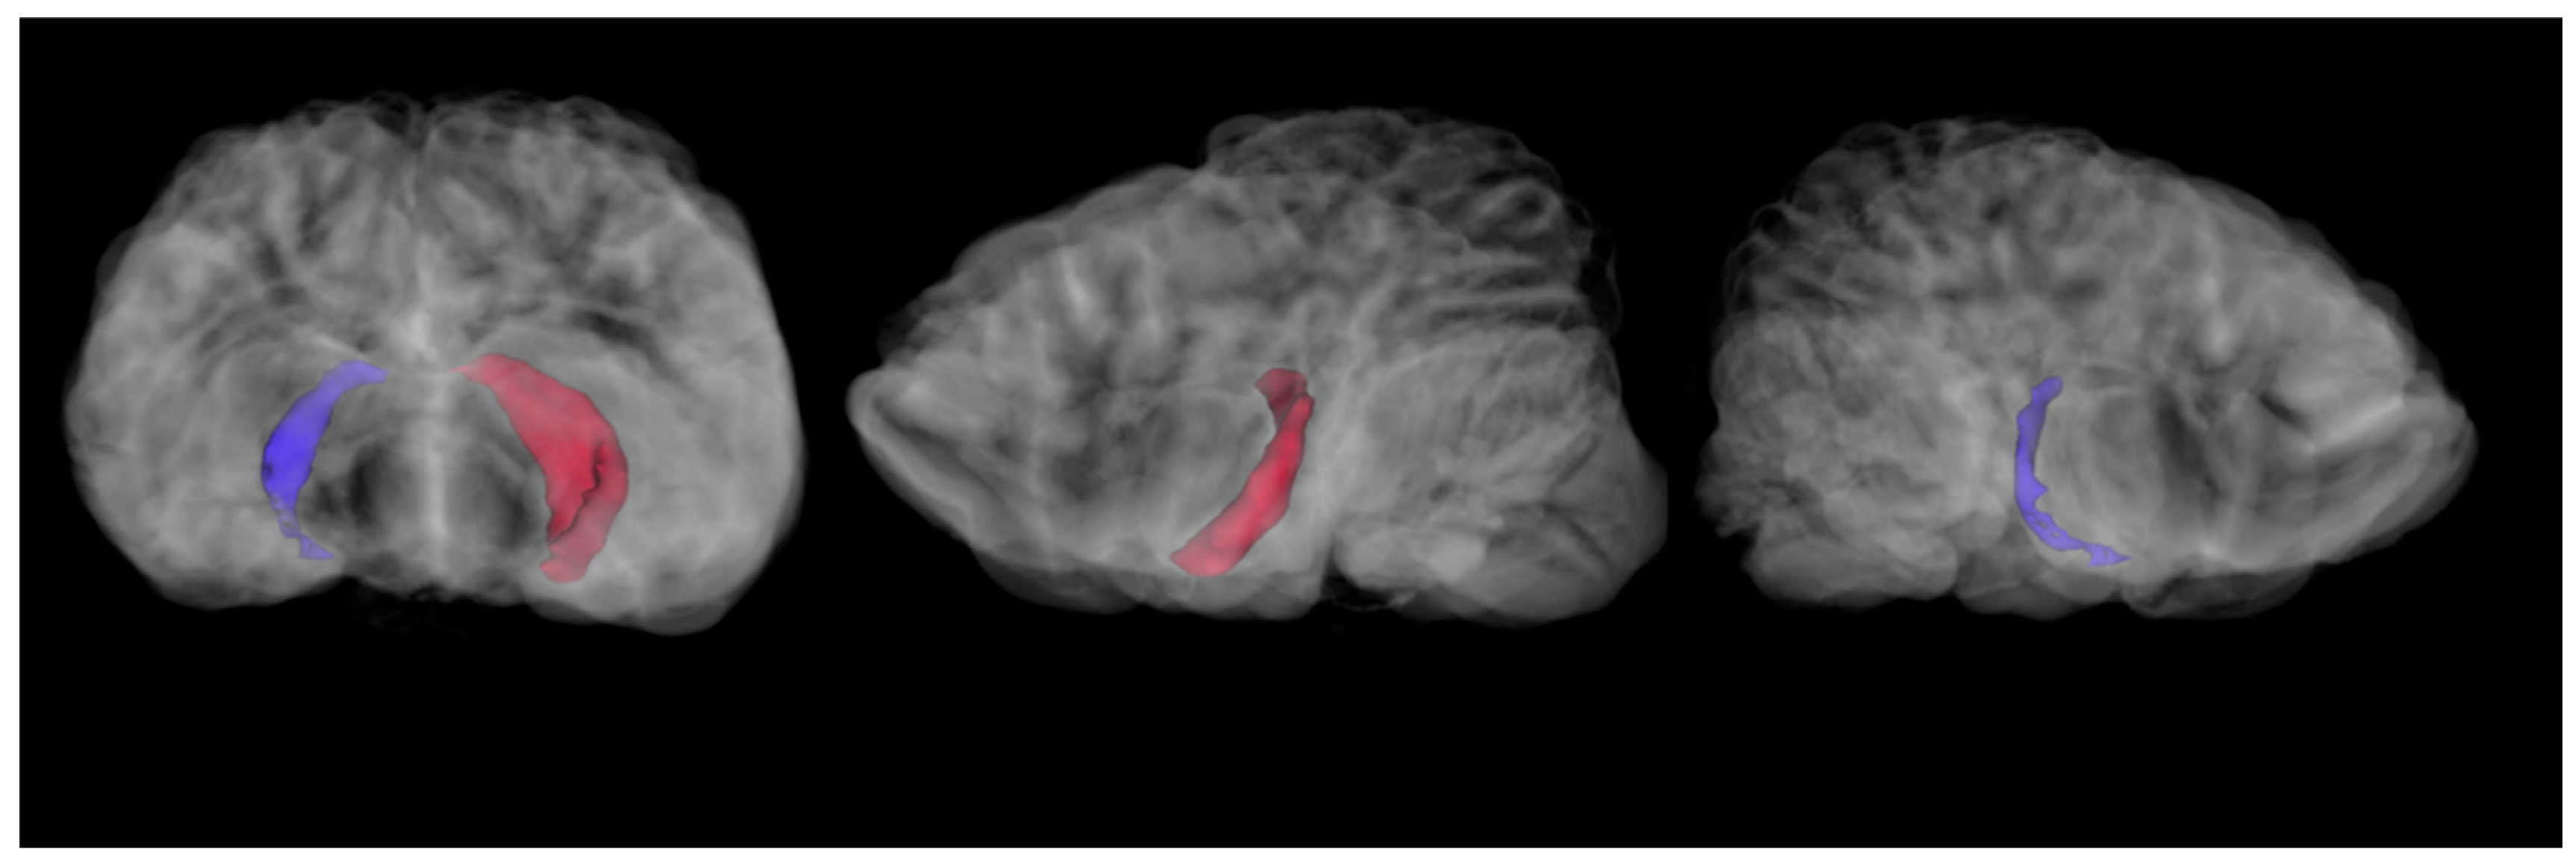

Hippocampal volumes were computed using the segment statistics module in 3D Slicer. For the 2021 imaging sequence, the right hippocampus was 273.6 mm3 and the left hippocampus was 879.6 mm3 (Figure 2).

A subsection of the 2021 hippocampal segmentations were compared to a matched slice from the 2001 imaging. The 2001 images were only available as MR films, so they were digitized. The digitized scans did not have voxel-by-voxel data preserved, so they could not be used for assessing specific volumetrics. To compare the 2001 scans with the 2021 scans, a representative slice of a proton density image sequence acquired in the dorsal plane was matched by multiple anatomical criteria to three contiguous slices in the 2021 T2 image sequence. The right and left hippocampi were traced in the 2001 scans, and then computed as a percentage of the total brain area for that slice. The average right and left hippocampal volume from the three comparable 2021 scans (acquired with much smaller voxels and thus thinner slices in all planes) were computed as a percentage of brain volume for those three slices. This allowed a meaningful comparison, although the underlying imaging geometry could not be precisely matched. In 2001, the section of the right hippocampus made up 0.39% of the total brain area in that slice, while the left hippocampus took up 0.38% of the area. In 2021, the right hippocampus took up 0.18% of the total brain volume for those slices and the left took up 0.47% (Figure 3).

Acknowledging the uncertainty due to inability to compute by-voxel volumetrics on the original image sequence, as well as the imperfectly matched scan orientation and necessity of comparing PD to T2 images, the relative tissue loss in the right hippocampus is very evident in the post-mortem scans. Interrater reliability was moderate to high for the four computed hippocampal volumes (2001 right: 74%, left: 74%; 2021 right: 72%, left: 87%). Notably, both raters measured the right hippocampus in the 2021 scan as having a far lower volume than the other three volumes (PC: 0.18, IM: 0.13). In addition, while there were signs of cerebellar encephalitis in the 2001 scan series, there was no evidence of gross cerebellar damage. In contrast, the left cerebellum showed evidence of atrophy in the 2021 scan series.

Figure 2. 2021 total HP volumes. Right (blue) and left (red) hippocampal segmentations displayed in transverse and sagittal perspectives left to right.